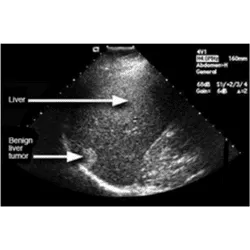

Imaging Tests: CT scan, Ultrasound, and MRI can give an idea about liver damage.

Examining Tissue Samples: Biopsy or removing tissue from the liver can help in identifying any kind of liver disease. This can also help in diagnosing any liver damage. It is done with a long needle inserted through your skin and removes liver tissue for sample testing.